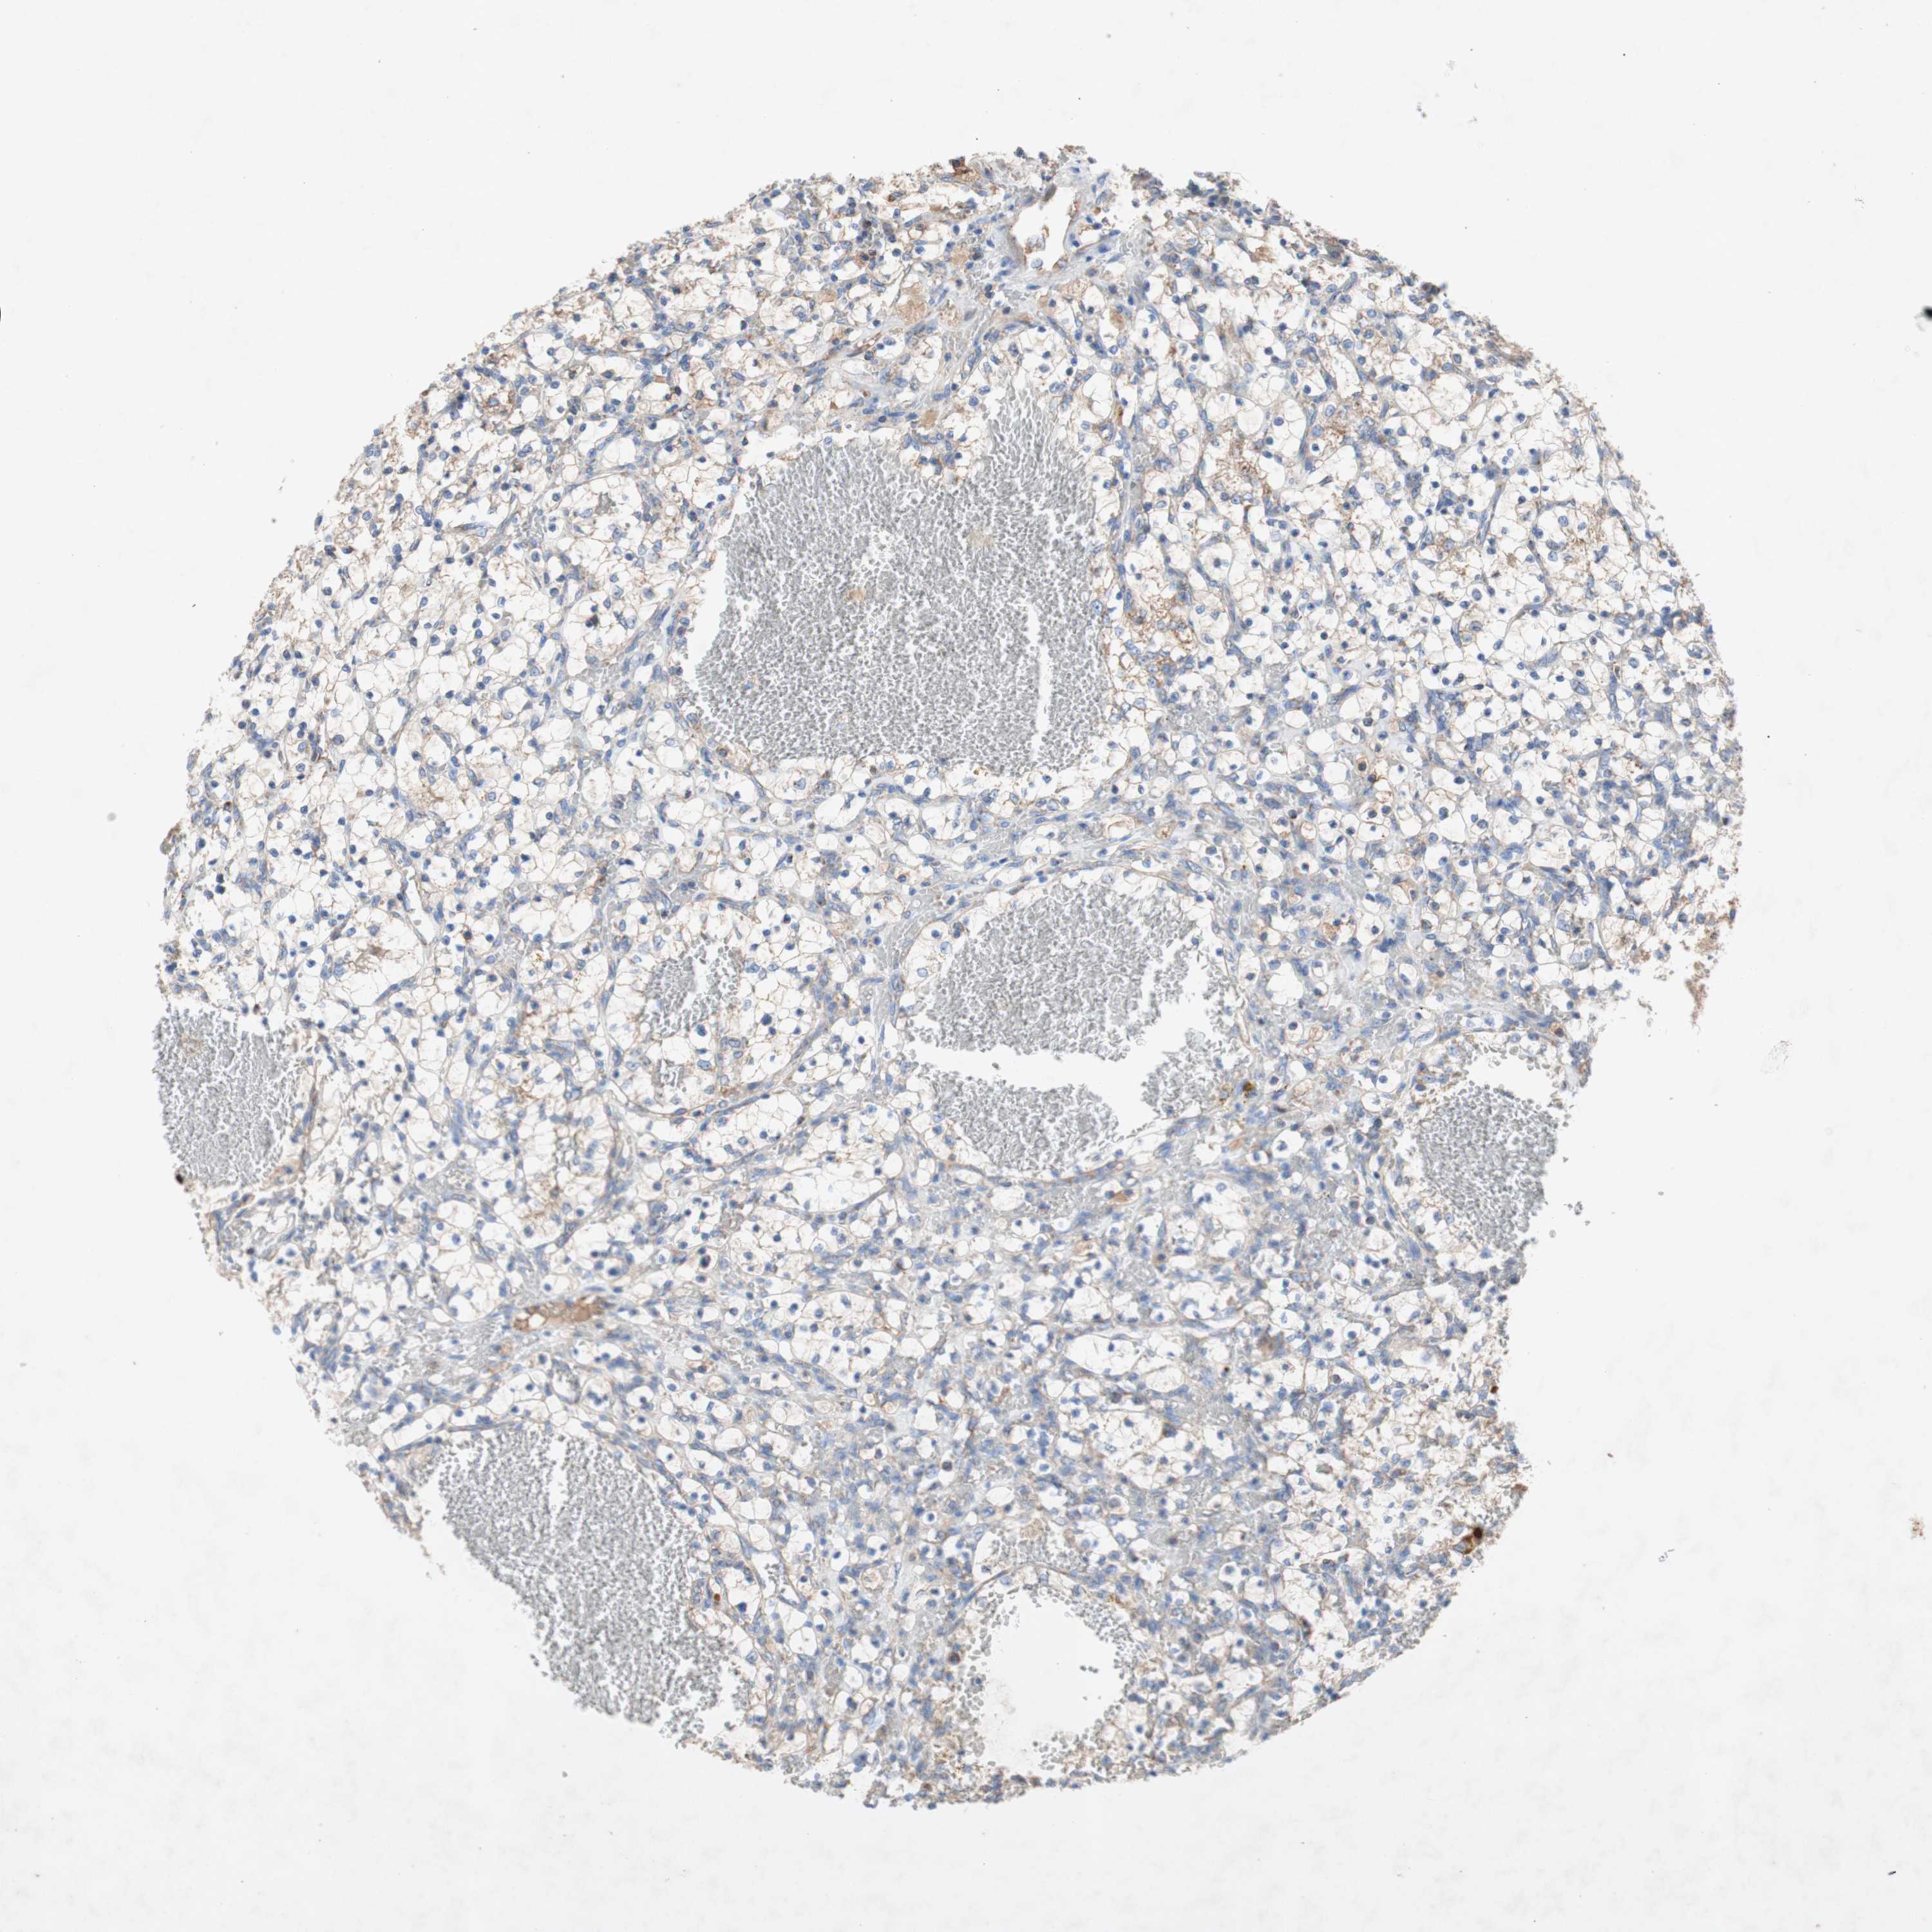

CANCER RENAL CANCER Show tissue menu

KICH TCGA KIRC TCGA KIRC VALIDATION KIRP TCGA PROTEIN RCC CPTAC PROTEIN EXPRESSION